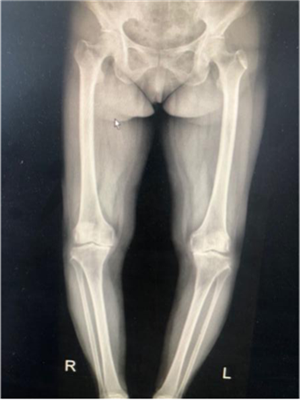

67歲的徐女士是陜北定邊縣人,10年來,她因?yàn)殡p膝關(guān)節(jié)疼痛,行走困難,不能上下樓梯,更無法像常人一樣下蹲,這給徐阿姨和她的家庭帶來了巨大的困擾。經(jīng)多方打聽,徐阿姨慕名找到張富軍主任,張主任詳細(xì)檢查后發(fā)現(xiàn)徐阿姨為雙側(cè)嚴(yán)重的骨關(guān)節(jié)炎并滑膜軟骨瘤病,需要進(jìn)行全膝關(guān)節(jié)置換術(shù)??紤]到患者有多種基礎(chǔ)病合并癥,張主任帶領(lǐng)其團(tuán)隊(duì)認(rèn)真研究后制定了詳細(xì)、周密的手術(shù)方案,做好圍手術(shù)期的準(zhǔn)備,決定采用最新技術(shù)的Vanguard CR E1假體雙膝膝關(guān)節(jié)置換術(shù)。

?。ㄊ中g(shù)前、手術(shù)后對(duì)比)